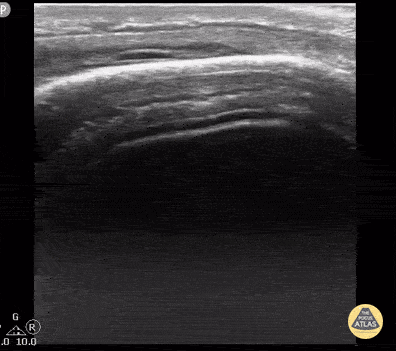

16 year old with large parietal hematoma and no underlying fracture. Bony cortex is intact. Contributor: Antonio Riera, MD